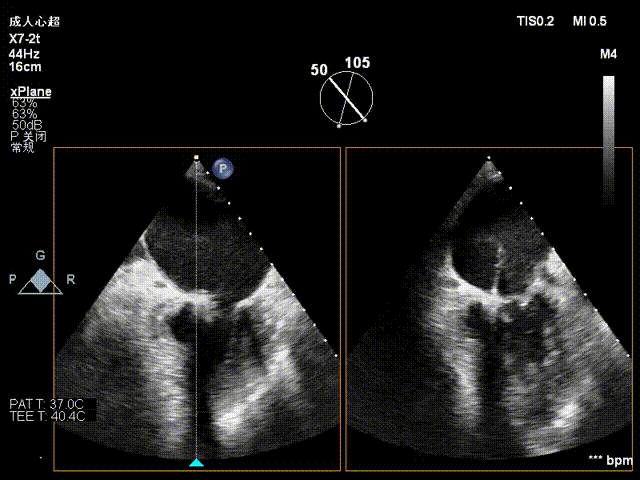

患者取平卧位,消毒铺巾后,穿刺右股静脉后置入6F血管鞘,经食道超声指导下进行房间隔穿刺,穿刺高度约4cm。

房间隔穿刺高度4cm

房间隔穿刺

NeoNova®C6(宽6mm)夹合器沿输送系统进入左房,调整夹合器orientation,夹合器抵达3区反流处。

进夹合器

进夹合器调弹道